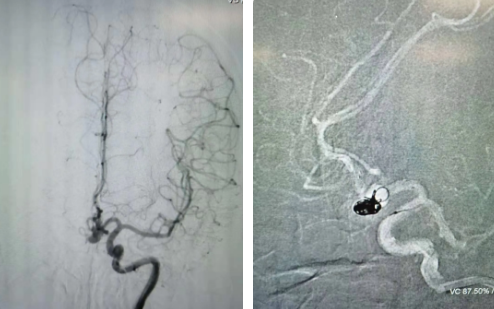

經(jīng)過全面仔細(xì)評(píng)估,西安國(guó)際醫(yī)學(xué)中心醫(yī)院神經(jīng)外科陸丹醫(yī)生決定采用微創(chuàng)介入進(jìn)行治療。在取得患者及家屬同意后,3月11日,陸丹醫(yī)生為患者行Atlas支架輔助顱內(nèi)動(dòng)脈瘤栓塞術(shù)。

腦血管較外周血管更為脆弱、迂曲,對(duì)術(shù)者的操作技術(shù)及精準(zhǔn)性要求特別高。術(shù)中,陸丹醫(yī)生通過股動(dòng)脈穿刺、置入微導(dǎo)管,再通過微導(dǎo)管將彈簧圏送入動(dòng)脈瘤腔內(nèi),利用彈簧圈的機(jī)械閉塞作用,達(dá)到防止動(dòng)脈瘤破裂的目的。術(shù)后,患者各項(xiàng)生命體征平穩(wěn)。

陸丹醫(yī)生介紹,此次腦科醫(yī)院首次采用Atlas支架輔助進(jìn)行顱內(nèi)動(dòng)脈瘤栓塞術(shù)。以往動(dòng)脈瘤栓塞術(shù)中的支架輸送導(dǎo)管較粗,支架順應(yīng)性差,易使載瘤動(dòng)脈移位,而Atlas支架的輸送導(dǎo)管很細(xì),輸送順滑,同時(shí)順應(yīng)性及貼壁性強(qiáng),能夠適應(yīng)迂曲的腦遠(yuǎn)端血管。